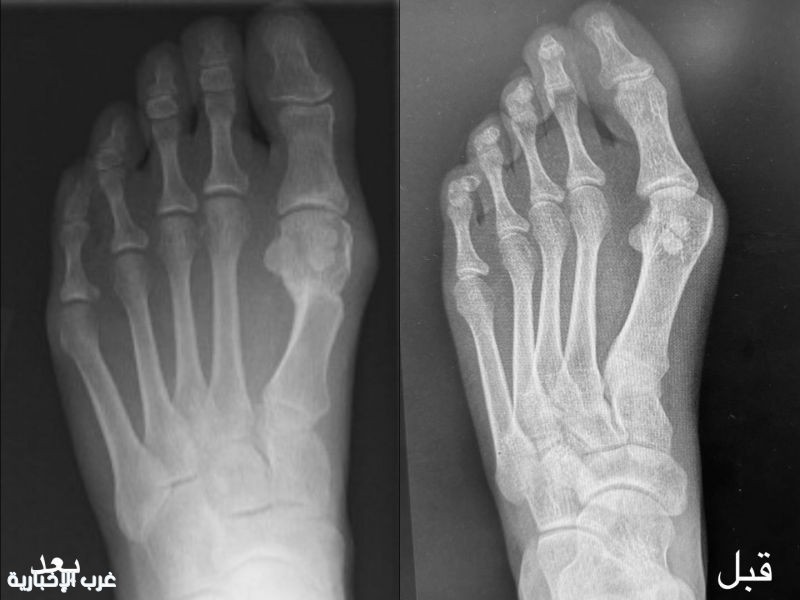

أنهى فريق طبي في قسم جراحة العظام بمستشفى الإمام عبدالرحمن الفيصل، عضو تجمع الرياض الصحي الأول، معاناة مريضة في العقد الثاني من عمرها، كانت تعاني من تشوّه متقدم وانحراف في إصبع القدم الكبير (Hallux Valgus)، مما أثر على حركتها وأنشطتها اليومية.

وأوضح رئيس قسم جراحة العظام وقائد الفريق الطبي، الدكتور عقيل محمد المهدلي، أن العملية نجحت باستخدام تقنية التدخل الجراحي المحدود (MIS)، بعد خضوع المريضة لسلسلة فحوصات سريرية وتشخيصية دقيقة، بما يضمن اتخاذ القرار الجراحي الأمثل.

وأضاف أن العملية أُجريت وفق أحدث المعايير الطبية، وأسفرت عن نجاح تام، مع الحفاظ على سلامة الأنسجة المحيطة وتقليل التدخل الجراحي قدر الإمكان. وأظهرت المتابعة بعد العملية تحسنًا ملحوظًا في وظيفة القدم، حيث أصبحت المريضة قادرة على المشي بشكل طبيعي، وممارسة الرياضة، وارتداء مختلف أنواع الأحذية دون آلام، مما انعكس إيجابًا على جودة حياتها وقدرتها على أداء أنشطتها اليومية.